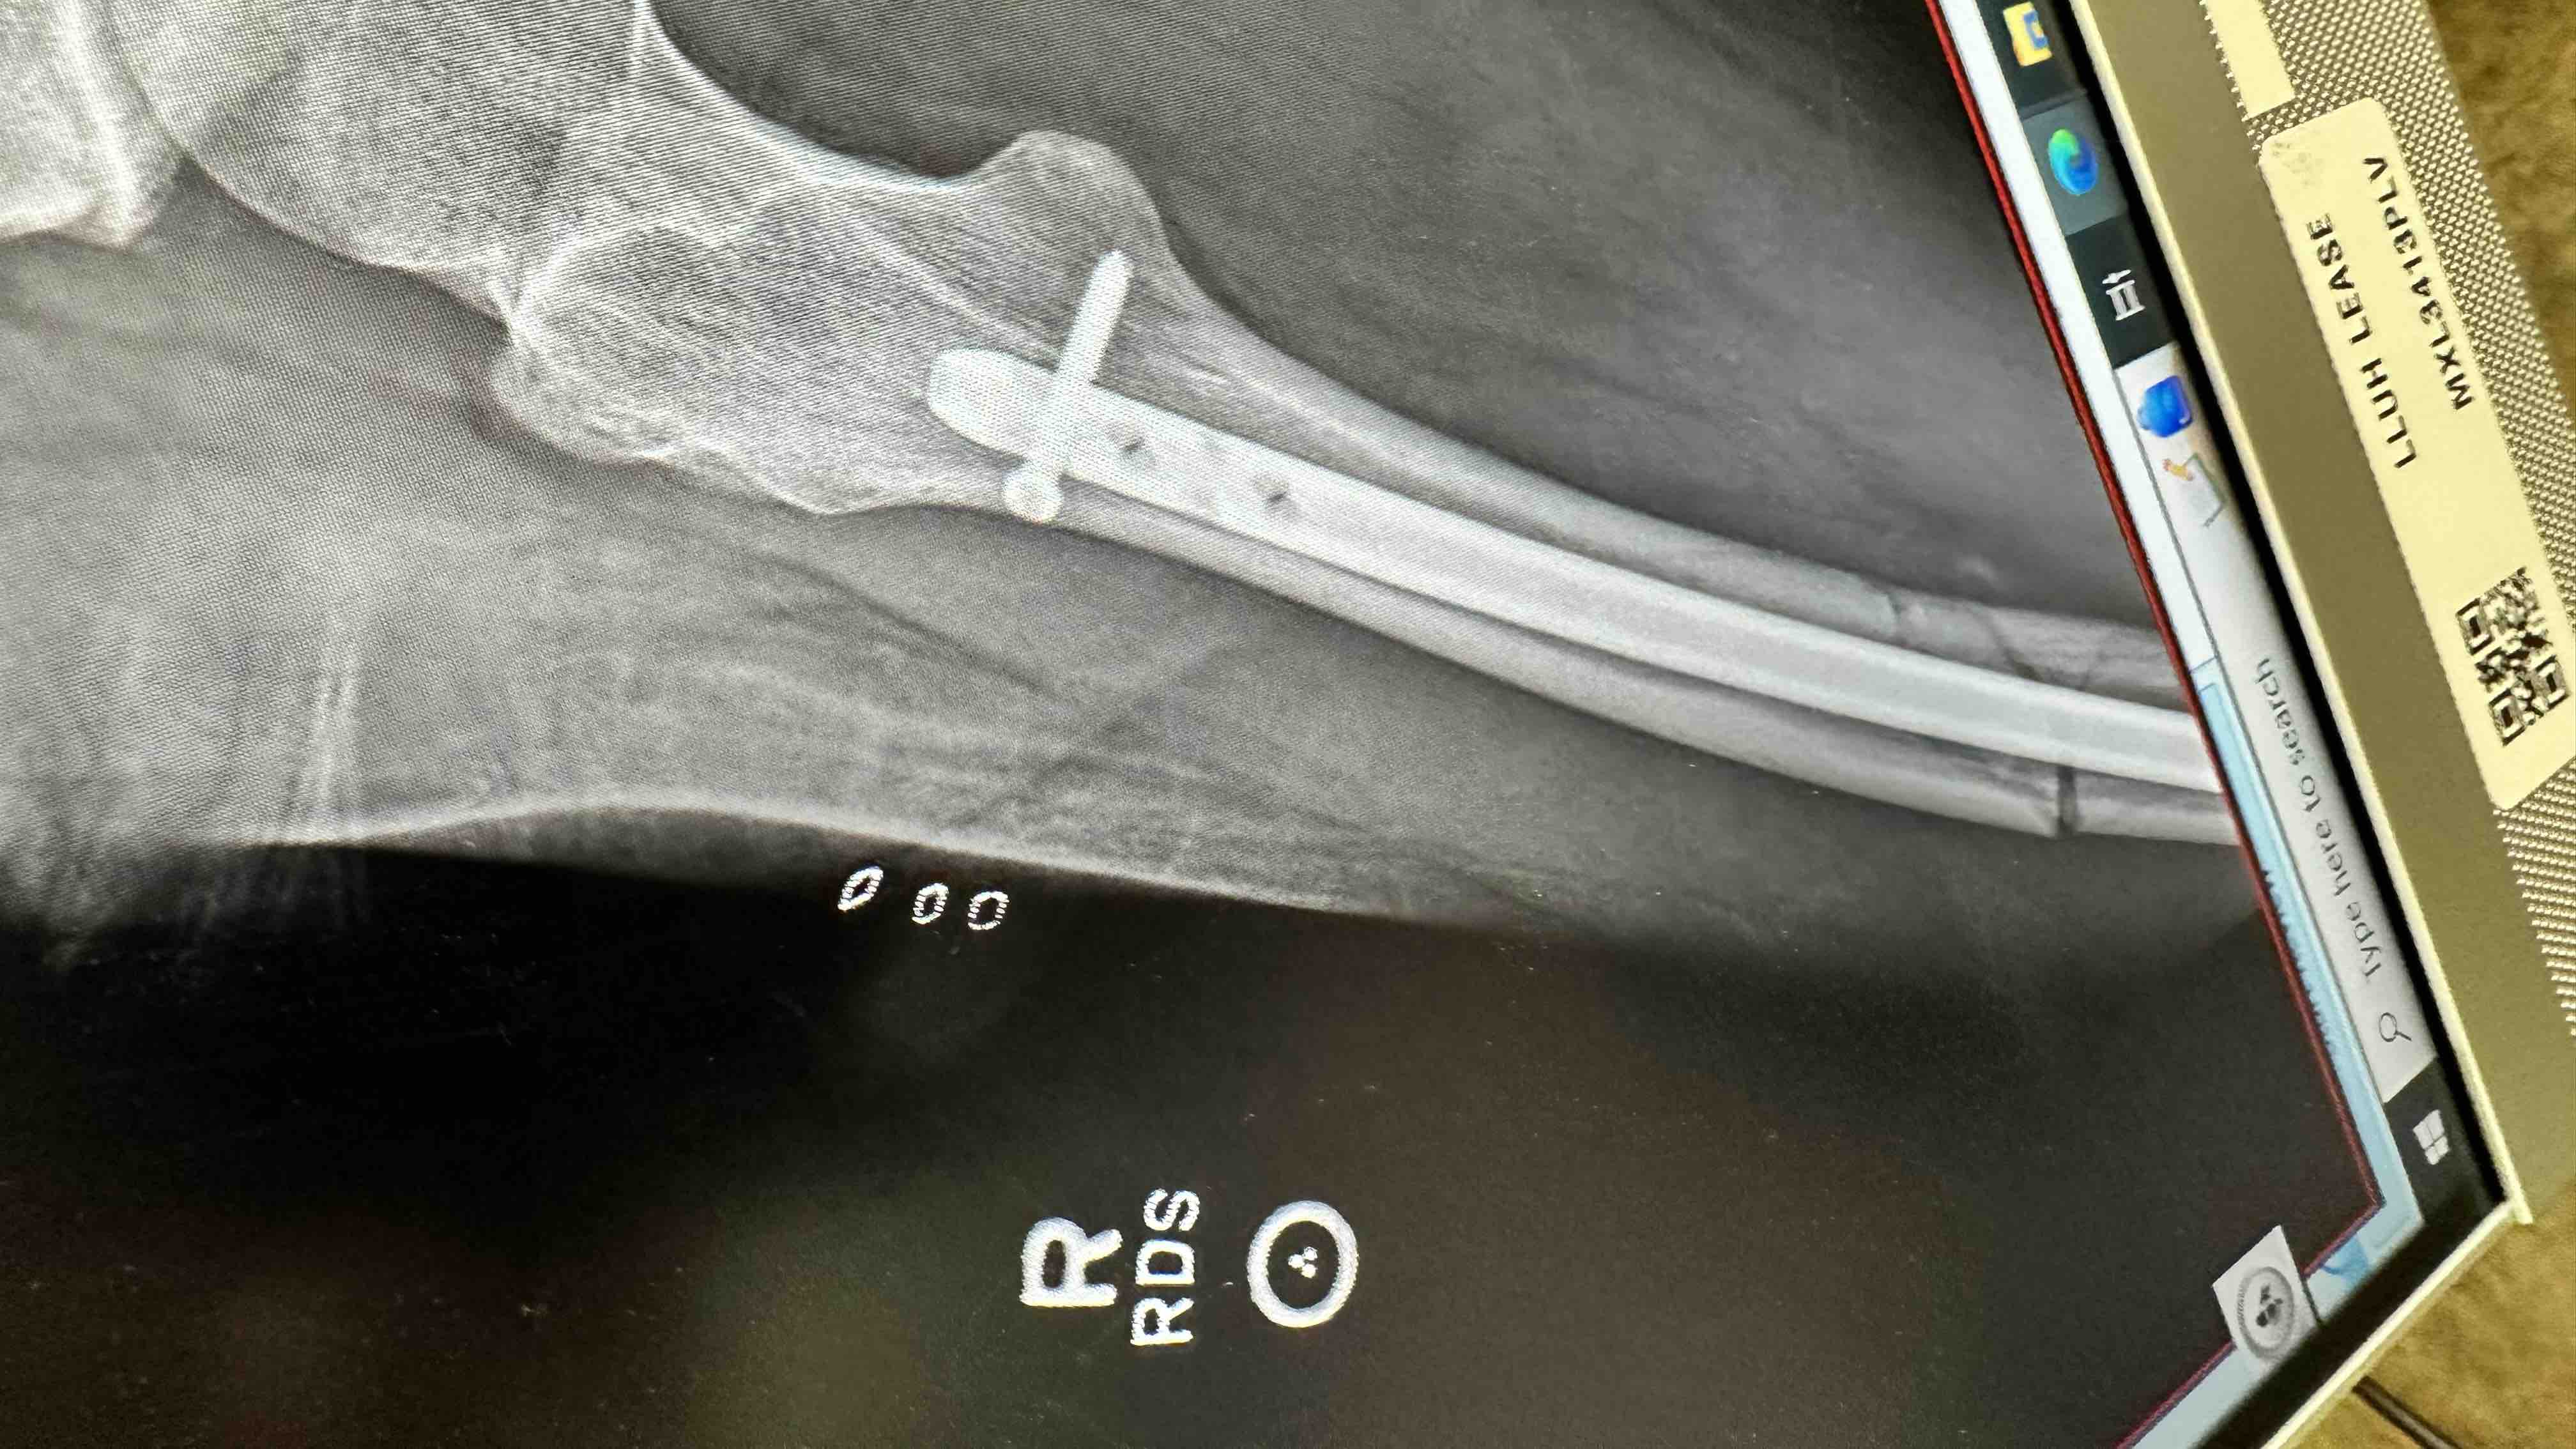

Hello my name is Hollis Grimes. I was in a horrible accident on February 29th, 2024 in Big Bear Ca. I launched 12 feet into the air off an icy rail, landed extremely hard resulting in a compound fracture to my femur, hairline fracture in my hip socket, and fractures in the spinous processes L 1-4. I was taken by ambulance to the local hospital in Big Bear and then transferred to Loma Linda Trauma Emergency Room. Within hours I had emergency surgery, placing a rod in my leg and pins in my knee. After a week in the hospital I began my long road to recovery of 9 months. I needed constant care as well as assistance with simple tasks like getting in and out of bed and could only sleep on my back with a protective device to prevent further injury. I was unable to walk for a month, then with a walker and now currently with a cane. Due to the accident I have not been able to return to work. Even with health insurance my medical bills and expenses are enormous. If you could assist me through this difficult time I would be eternally grateful. Thank you so much.